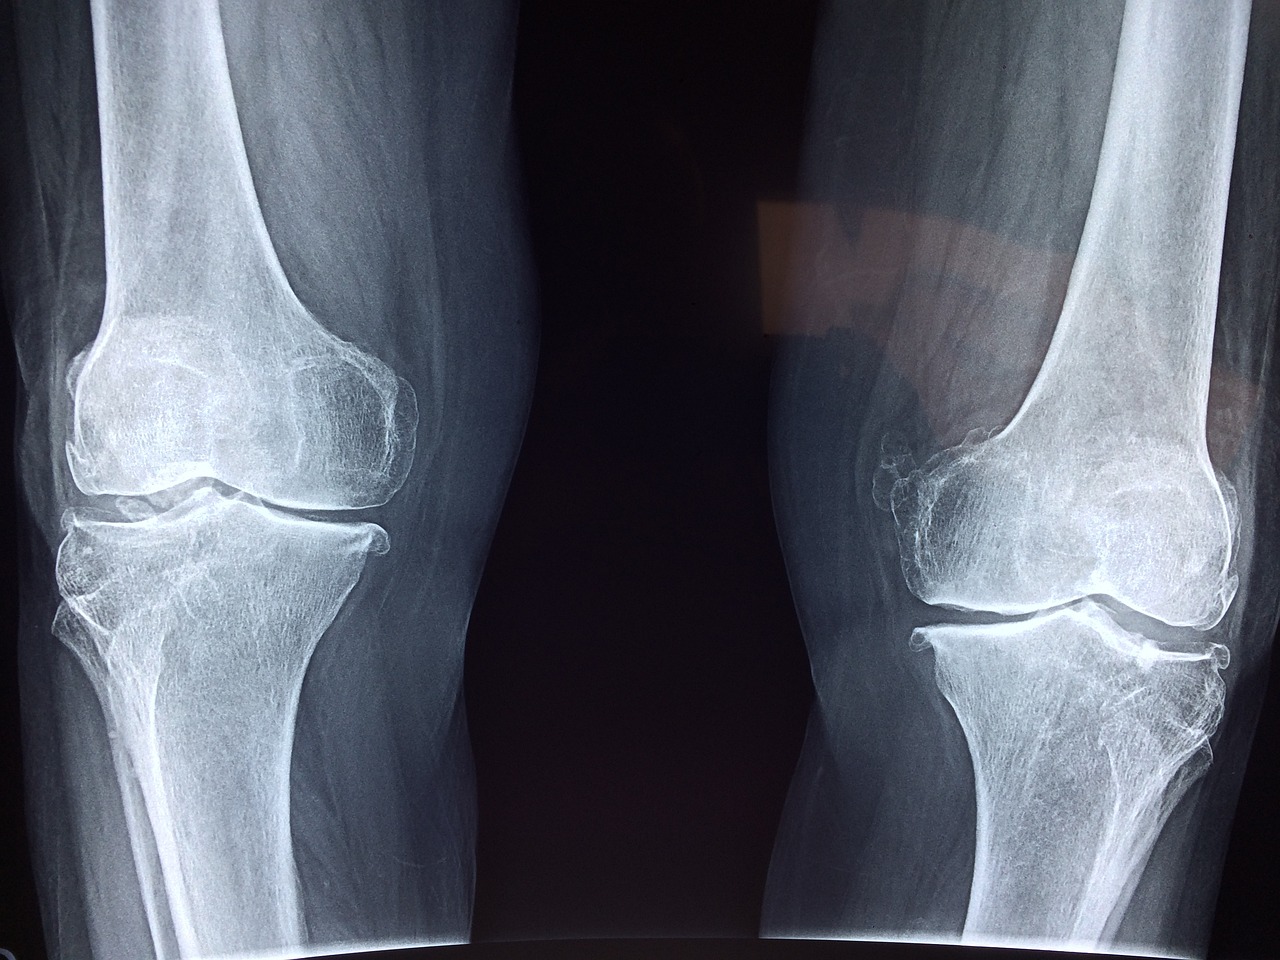

📌 왜 무릎에 무리가 갈까요?

✅ 달리기 시 무릎 관절은 체중의 7~9배 무게를 지탱해야 합니다.

✅ 과체중·비만이면 무릎에 가해지는 압력이 더욱 커져 관절 손상이 심해집니다.

✅ 비만한 사람은 정상 체중보다 ‘무릎 관절 수술’ 확률이 40% 더 높습니다.